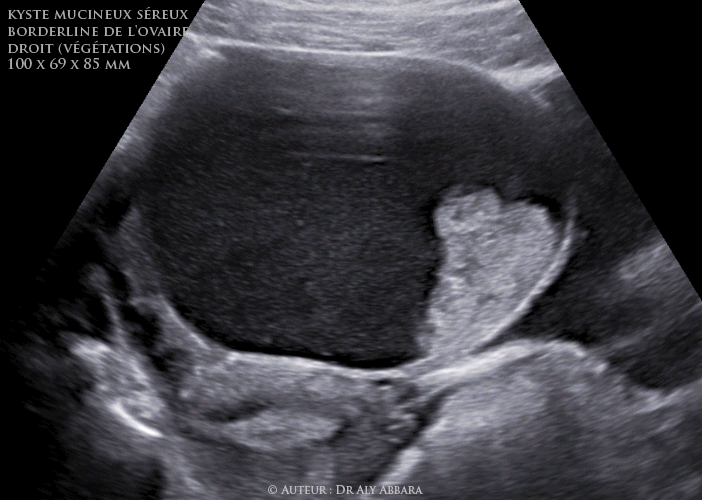

Il s'agit échographiquement d'une volumineuse tumeur ovarienne kystique de 100 x 69 x 85 mm de diamètre (environ 305 cm3 de volume), uni-loculaire, à contenu hypoéchogène, avec la présence de deux végétations endophytiques, le plus volumineuse mesure 5 cm de hauteur et 4 cm de base d'implantation ; l'autre végétation est de 2 cm de hauteur. L'étude des signaux Doppler montrent qu'il s'agit de végétations endophytiques vascularisées et comportant de micro-veines et micro-artérioles, cela permet de confirmer leur nature tumorale et les distinguer de caillaux sanguins endokystiques.

L'ovaire droit est d'aspect tumoral, mesurant environ 10 cm de grand axe, non adhérentiel, à surface lisse, sans végétation exophytique. Pas d'ascite ni d'implants péritonéaux tumoraux.

A la coupe anatomopathologique (annexectomie totale droite) : il s'agit d'une tumeur évoluant au sein de l'ovaire droit, uniloculaire à contenu liquidien mucoïde avec paroi interne bourgeonnant : présence de deux volumineuses végétations endophytiques de 5 et 2 cm de hauteur correspondant histologiquement à une prolifération de tissu épithéliale papillaire mixte, à la fois muco-sécrétoire de type cervical et également de d'épithélium de type séreux, parfois pluristratifié avec des atypies cytonucléaires modérées et rares mitoses. Absence de micro-invasion au niveau des axes papillaires.